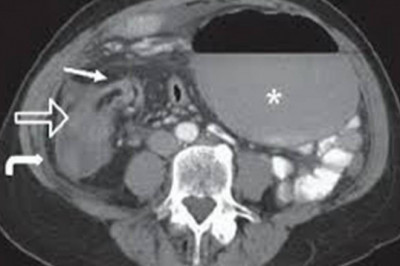

NATURAL TREATMENT FOR CECAL VOLVULUS

The longest organ a human body houses is the intestines of the alimentary canal ,you may be amazed by the fact that when our intestines are fully stretched out, it reaches about 20 feet long. We are all unique, our intestines need different foods and our...